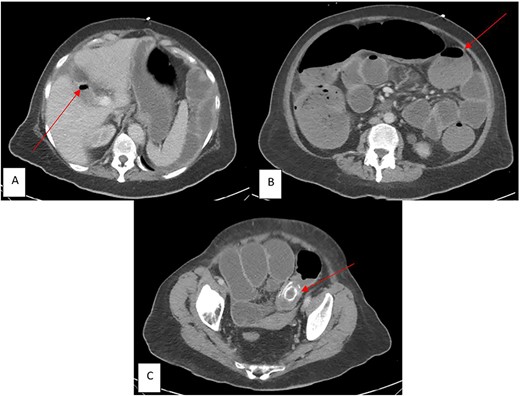

A 69-year-old Caucasian female presented to our institution with a chief complaint of abdominal pain with accompanying nausea, vomiting and constipation for ⁓1 week. Patient was noted to have multiple co-morbidities: chronic obstructive pulmonary disease (COPD), heart failure with reduced ejection fraction (HFrEF), and a recent middle cerebral artery (MCA) ischemic stroke. Vitals were significant for body temperature of 36.7°C, blood pressure was 91/56 mmHg, and pulse rate was 104 beats/min. On a physical exam, the patient displayed tenderness to palpation in the left lower quadrant of her abdomen with abdominal distention and tympany to percussion. Laboratory studies significant for leukocytosis [white blood cell count (WBC) 16.2 u/L] and electrolyte abnormalities (Potassium 3.0 mEq/L, Chloride 102 mEq/L). CT revealed pneumobilia (Fig. 1A), multiple distended loops of bowel consistent with obstruction (Fig. 1B), and a 3.6 × 2.1 cm, high-density structure within the lumen of the distal sigmoid colon indicating impacted gallstone (Fig. 1C). Based on these clinical findings, the patient was diagnosed with sigmoid GI. Considering the risk of perforation and patient’s hemodynamic instability, an emergent laparotomy was performed.

CT imaging in the emergency department (ED) with components of Rigler’s Triad (marked by red arrows): (A) Pneumobilia, (B) distended loops of bowel consist with large bowel obstruction, (C) gallstone impacted in the sigmoid colon.